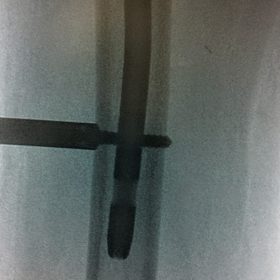

Διατροχαντήριο : Εξωαρθρικό κάταγμα, στην περιοχή ανάμεσα στο ελάσσονα και το μείζονα τροχαντήρα. Αντιμετωπίζεται χειρουργικά με ενδομυελική ήλωση τύπου γ-Nail. Δύο τομές 3 εκατοστών και 1 εκατοστού αντιστοίχως για την εισαγωγή και το κλείδωμα του ήλου μέσα στο οστό. Η μέθοδος είναι κλειστή,σχεδόν αναίμακτη,διάρκειας 30 λεπτών,με τη βοήθεια C-ARM (τηλεόρασης). Στον ασθενή παρέχεται οπτικό υλικό (όλα τα χειρουργικά στάδια) σε CD ή Στικάκι,λόγω της δυνατότητας καταγραφής του χειρουργείου από το C-ARM Ο ασθενής περπατάει άμεσα μετεγχειρητικά στις 5 ώρες μετά την επέμβαση και εξέρχεται από το νοσοκομείο σε 1 -2 ημέρες.

Υποτροχαντήριο :Εξωαρθρικό κάταγμα κάτω από τον ελάσσονα τροχαντήρα του μηριαίου οστού. Αντιμετωπίζεται χειρουργικά με ενδομυελική ήλωση τύπου Long γ-Nail. Δύο τομές 3 εκατοστών και 1 εκατοστού αντιστοίχως για την εισαγωγή και το κλείδωμα του ήλου μέσα στο οστό. Η μέθοδος είναι κλειστή,σχεδόν αναίμακτη,διάρκειας 60 λεπτών,με τη βοήθεια C-ARM (τηλεόρασης). Στον ασθενή παρέχεται οπτικό υλικό (όλα τα χειρουργικά στάδια) σε CD ή Στικάκι,λόγω της δυνατότητας καταγραφής του χειρουργείου από το C-ARM Ο ασθενής περπατάει άμεσα μετεγχειρητικά στις 5 ώρες μετά την επέμβαση και εξέρχεται από το νοσοκομείο σε 1 -2 ημέρες.